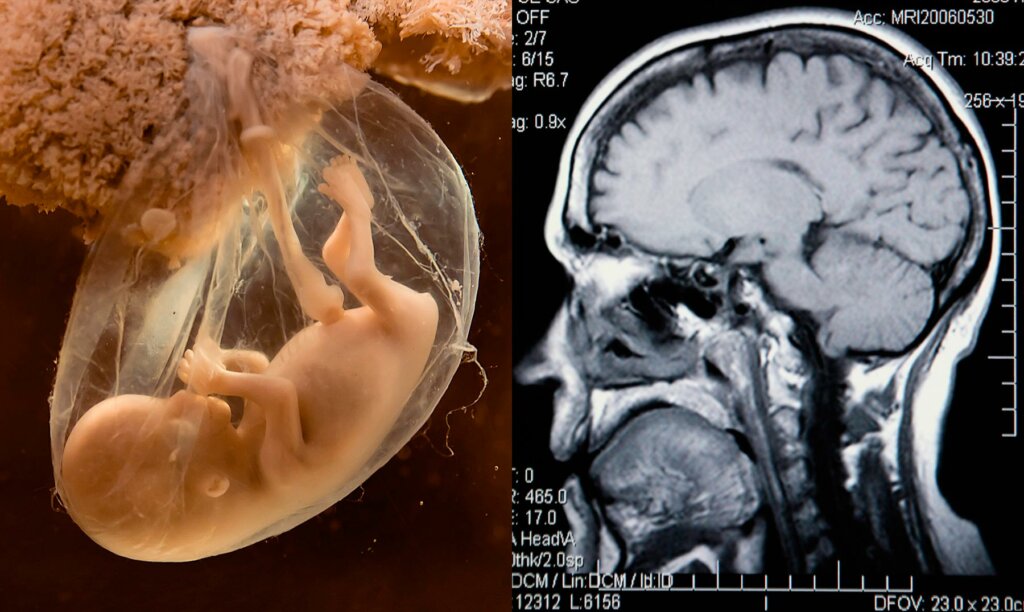

Fødselsdepresjon har fått synlighet de siste årene, og ødelegger myten om at perioden etter svangerskapet alltid er en lykkelig tid. Når det er sagt, kan depresjon også utvikle seg før en kvinne blir gravid eller under graviditeten. Faktisk inkluderer begrepet perinatal depresjon depresjon under graviditet og innen et år etter fødsel.

Svangerskaps- eller fødselsdepresjon rammer omtrent én av åtte kvinner. Disse to begrepene har en tendens til å bli brukt om hverandre. Det førstnevnte begrepet gjelder imidlertid mer spesifikt kvinner. Lidelsen vedvarer ofte gjennom barselsperioden. Faktisk har opptil 47 prosent av kvinnene med fødselsdepresjon opplevd en episode under svangerskapet.

Perinatal depresjon er assosiert med et spekter av negative langsiktige obstetriske utfall hos avkom. Disse inkluderer potensielle negative innvirkninger på mor-spedbarn-forholdet. Det påvirker også i stor grad kvinners velvære og funksjon og kan til og med føre til selvmord. I moderate til alvorlige tilfeller, eller etter manglende respons på førstelinje psykoterapi, er farmakoterapi med antidepressiva ofte nødvendig. Sammenslåtte resultater fra 40 kohortstudier indikerer at selektive serotoninreopptakshemmere (SSRI) er de mest brukte antidepressiva.